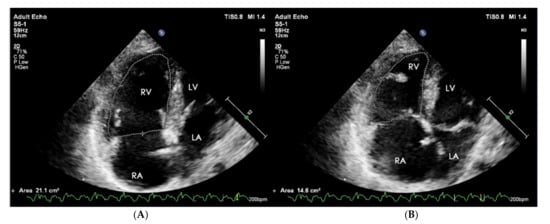

The equivalent of RVEF is the functional area change (FAC) of RV. It is a parameter of a proven clinical significance that has been recognized as a prognostic indicator of heart failure and sudden cardiac death in the course of PAH [47]. Its value is determined as a percentage after calculating the diastolic-systolic quotient of the difference in RV area and its diastolic area in the 4CH view (Figure 9). Normally it should exceed 35%, and lower values indicate RV systolic dysfunction [48].

Figure 9.

(A) End-diastolic volume RV = 21.1 cm2, (B) end-systolic volume RV = 14.6 cm2. FAC = 30.8%. FAC = A(diast) − A(sys)/A(dias) * 100%. 2D-TTE, 4CH view. RV: right ventricle; FAC: functional area change; 2D-TTE: two-dimensional transthoracic echocardiography; 4CH: four-chamber.